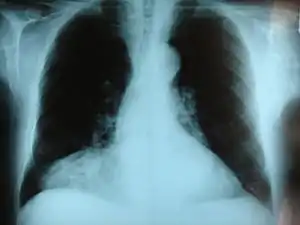

![]() | |

| Morgagni hernia seen on a chest radiograph. | |